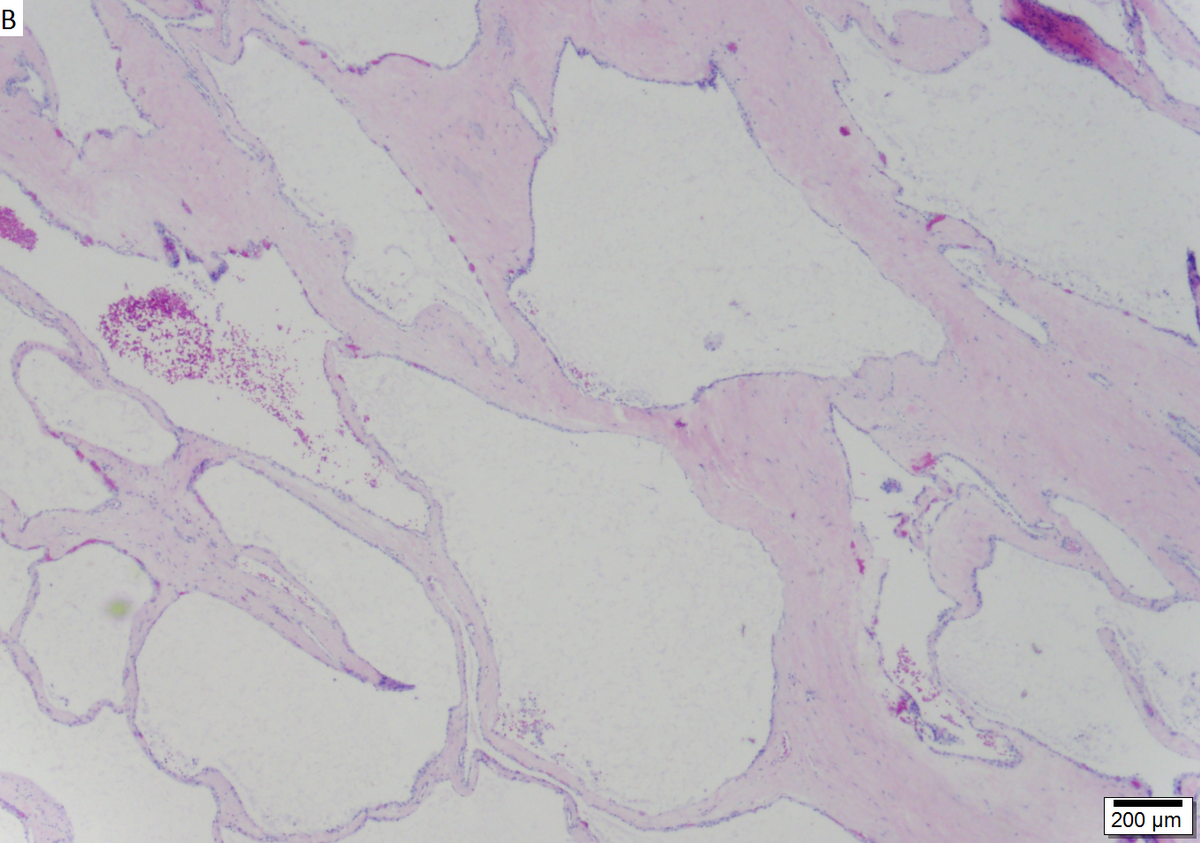

Microcystic serous cystadenoma of pancreas in a 62 year old woman. A. The tumor showed a central scar with multiple minute cysts; slight pressure yielded clear fluid. B. The mass comprises microcysts numberless. C. Cysts bear single cell linings with bland, amitotic nuclei. D. PAS without diastase shows positive cytoplasmic material. E. PAS with diastase shows the cytoplasmic material has been digested away. F. Keratin shows positive staining lining cells.

LM small cystic spaces lined by cytologically bland cuboidal cells

• Cystic spaces lined by cuboidal cells.

• Glycogen rich.